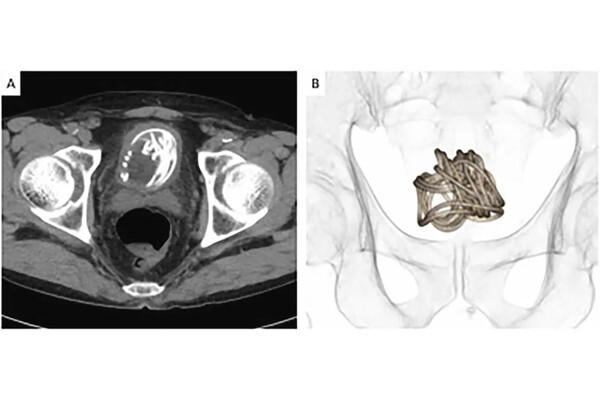

Медики хотели изъять инородное тело через уретру, однако рентген показал, что скакалка скрутилась в большой комок. В результате, чтобы вытащить веревку, хирургам пришлось разрезать мочевой пузырь.

Перед этим врачи сделали несколько подробных снимков КТ, чтобы определиться, где лучше сделать разрез. В своем отчете медики заявили, что этот инцидент продемонстрировал «неоценимую» пользу использования 3D-реконструкций для подготовки к проведению операций на мочевом пузыре.